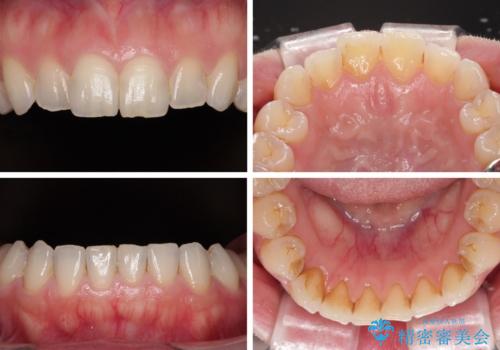

変色している歯をとにかく白く 全顎セラミック治療

- 奥歯の銀歯をセラミックにしたいとのことで来院された患者様です。

当初は奥歯のみの治療をご希望でしたが、話を進めていくうちに、軽度ではあるものの、幼少期の薬の影響で歯が変色していることがコンプレックスであるということが分かりました。

長年歯の色が塞ぎ込んでいた部分があるとのことで、これを機会に全ての歯を真っ白にするために、オールセラミッククラウンにて補綴治療を行うこととしました。

より白さが目立つように、自然な仕上がりではなく、作り物の雰囲気があるフルジルコニアクラウンにて補綴治療を行いました。